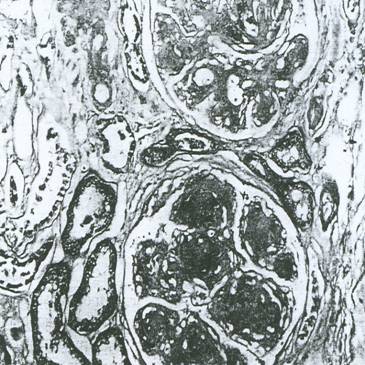

a). Leziunile nodulare - descrise de Kimmelstiel Wilson (Figura 5.10), au fost considerate

mult timp ca fiind caracteristice nefropatiei diabetice. Mecanismele de formare a acestor noduli nu sunt elucidate. Se incrimineaza atat procesele de mezangioliza focala [117] cat si cele de necroza fibrinoida [32]. Se caracterizeaza prin aparitia de noduli hialini acelulari, cu aspect fibrilar. Nodulii sunt bine demarcati, eozinofili, localizati in regiunile centrale ale lobulilor glomerulari. Ei sunt frecvent incercuiti de celule spumoase. Sunt relativ omogeni la coloratia cu hematoxilina si au o structura laminata dupa coloratia cu acid-Schiff periodic. Caracteristicile acestui tip de leziuni sunt: neregularitatea marimii si distributiei in si intre glomeruli si localizarea lor departe de hil. Probabil locul lor de origine este mezangiul. Distrugerea mezangiala si liza centrului lobular este corelata cu dilatarea capilara microanevrismala, urmata de reorganizarea laminara a ramasitelor mezangiale. Formarea nodulilor este inalt specifica pentru glomerulopatia diabetica, dar alte boli renale, cum ar fi glomerulonefrita mezangiocapilara, nefropatia amiloida, boala lanturilor usoare s.a., pot fi asociate cu anormalitati nodulare. Microscopia electronica si studiile in imunofluorescenta aduc elemente distincte in nefropatia diabetica [96]. Este general acceptat ca nodulii nu sunt prezenti in absenta leziunilor difuze si apar numai dupa o lunga perioada de boala (aproximativ 14 ani). Nodulii Kimmelstiel Wilson nu sunt totdeauna prezenti in nefropatia diabetica. Prevalenta lor variaza considerabil, intre 12 - 55%.

Figura 5.10. Glomeruloscleroza nodulara (Kimmelstiel Wilson)